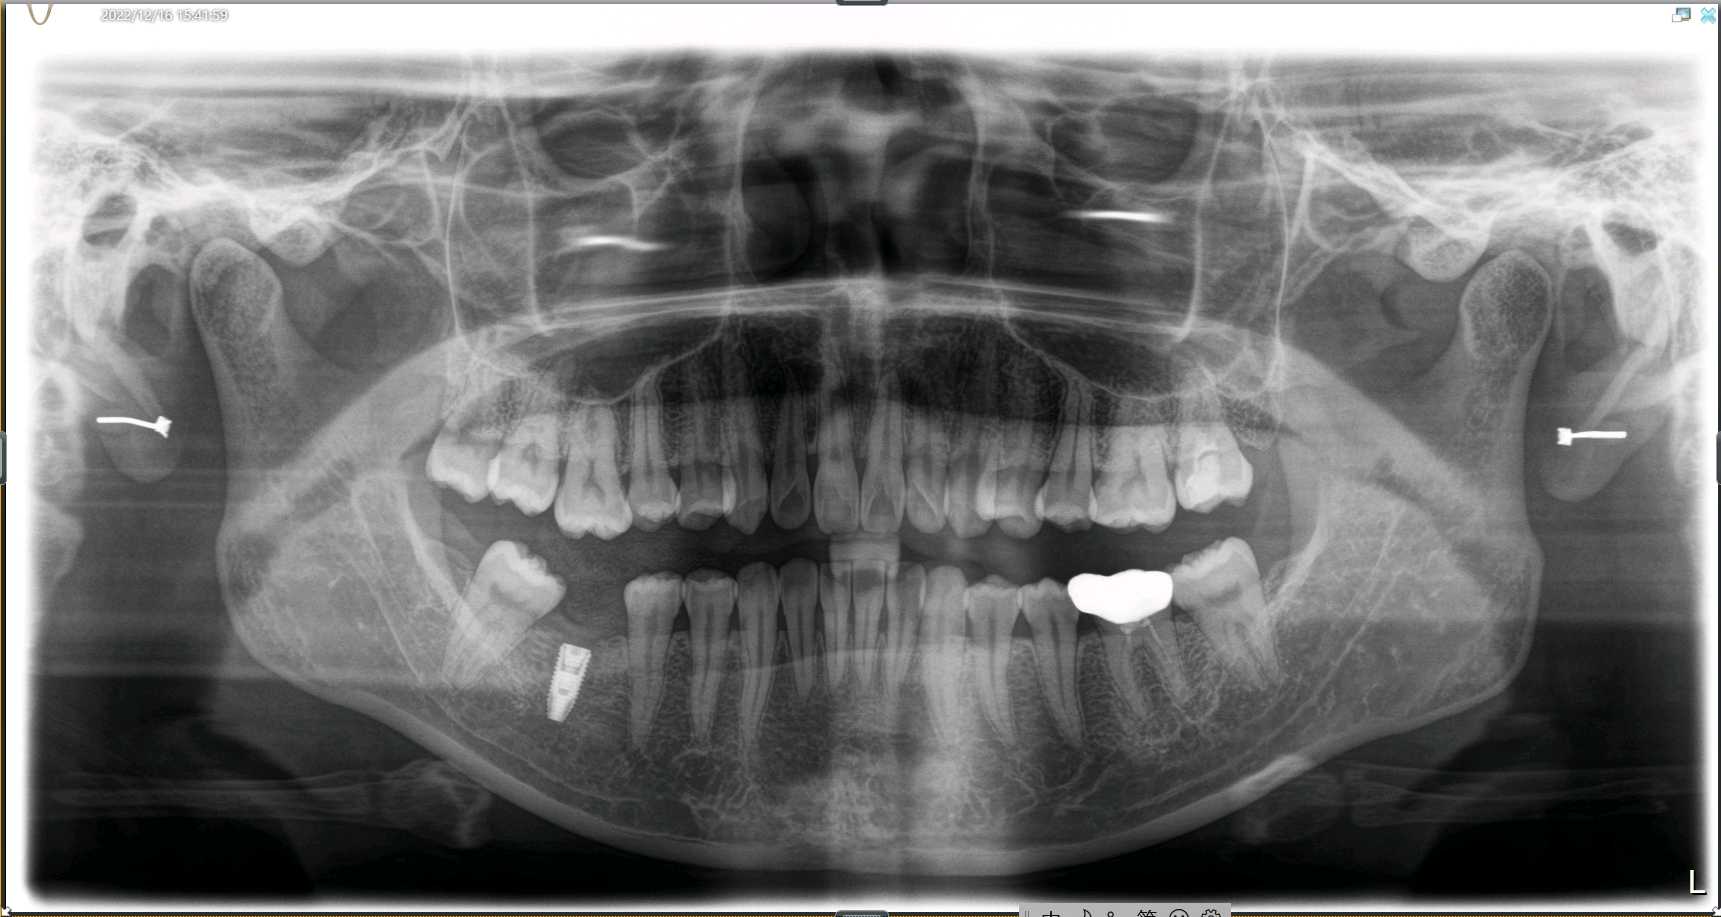

患者女,二十七岁,46牙体缺失近一年,牙槽崎吸收较多,粘膜无红肿、对合牙轻度伸长,邻牙轻微松动,龈周﹣。 x 示牙槽骨密度正常。告知患者治疗方案,患者选择种植修复。抽静脉血20ml,制作 CGF ,植Nobel Pcc 种植体4.3*10mm,上覆盖帽,颊侧骨缺损区植入 bio - oss 骨粉0.25g及 CGF ,盖 bio - Gide 膜及 CGF 膜,严密缝合。直至今日戴牙,咬合适宜,患者满意。